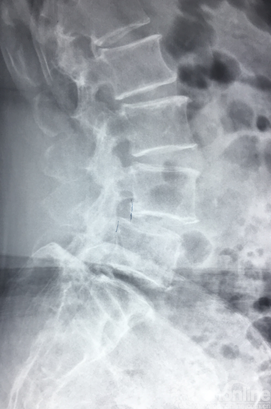

侧位X片